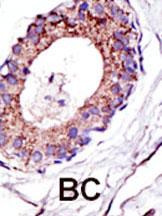

Formalin-fixed and paraffin-embedded human cancer tissue reacted with the primary antibody, which was peroxidase-conjugated to the secondary antibody, followed by DAB staining. This data demonstrates the use of this antibody for immunohistochemistry; clinical relevance has not been evaluated. BC = breast carcinoma; HC = hepatocarcinoma. |